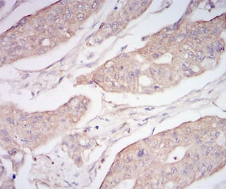

CD10 Mouse Monoclonal antibody[5E9A5]

IHC    1/200 - 1/1000